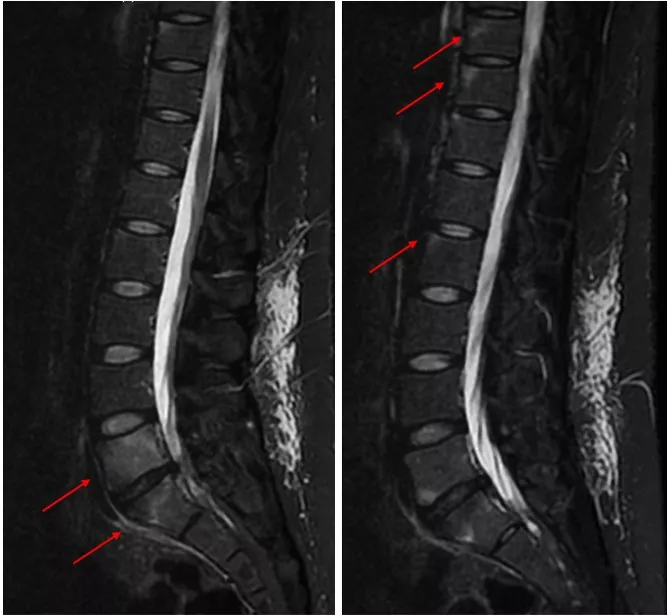

追加の病歴聴取で先行感染症歴や慢性的な下痢や血便なし。身体所見では全身に皮疹は認めず、爪の変形なし。血液検査ではリウマトイド因子陰性、抗CCP抗体陰性、抗核抗体陰性。HLA-B27は陰性。関節超音波検査で末梢関節に滑膜炎や付着部炎は認めず。単純X線で仙腸関節に明らかなびらん、骨硬化、狭小化なし(写真2)。仙腸関節CTでは右仙腸関節にびらん及び骨硬化を示唆する所見あり(写真3)。

写真2 仙腸関節Xp